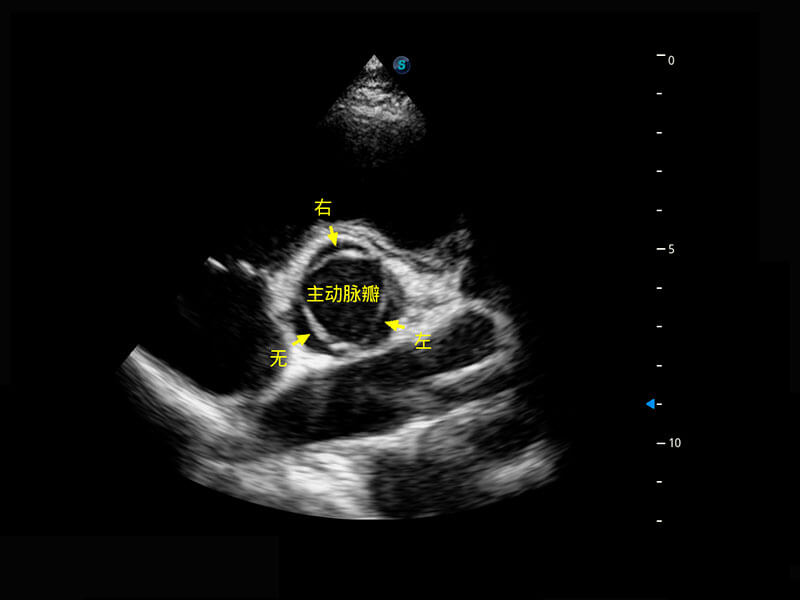

P60搭載一系列胎兒心臟成像技術(shù),實(shí)現(xiàn)精細(xì)的胎兒心臟評(píng)估。

四腔切面

右室雙出口